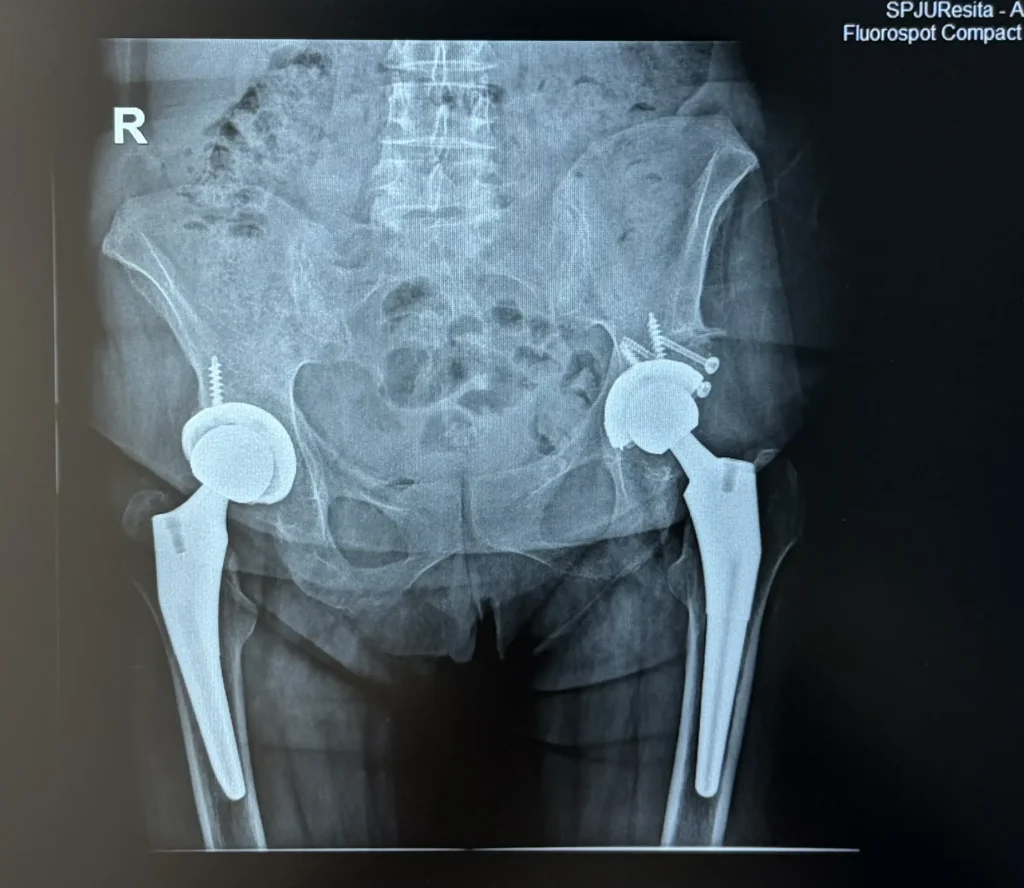

Pacienta, în vârstă de 56 de ani, s-a prezentat cu displazie coxală severă la șoldul stâng și coxartroză avansată la șoldul drept, asociate cu o scurtare a membrului inferior de aproximativ 2 cm.

După o evaluare atentă și planificare chirurgicală individualizată, am decis efectuarea unei artroplastii totale de șold bilateral, în doi timpi operatori, la un interval de aproximativ două luni între intervenții.